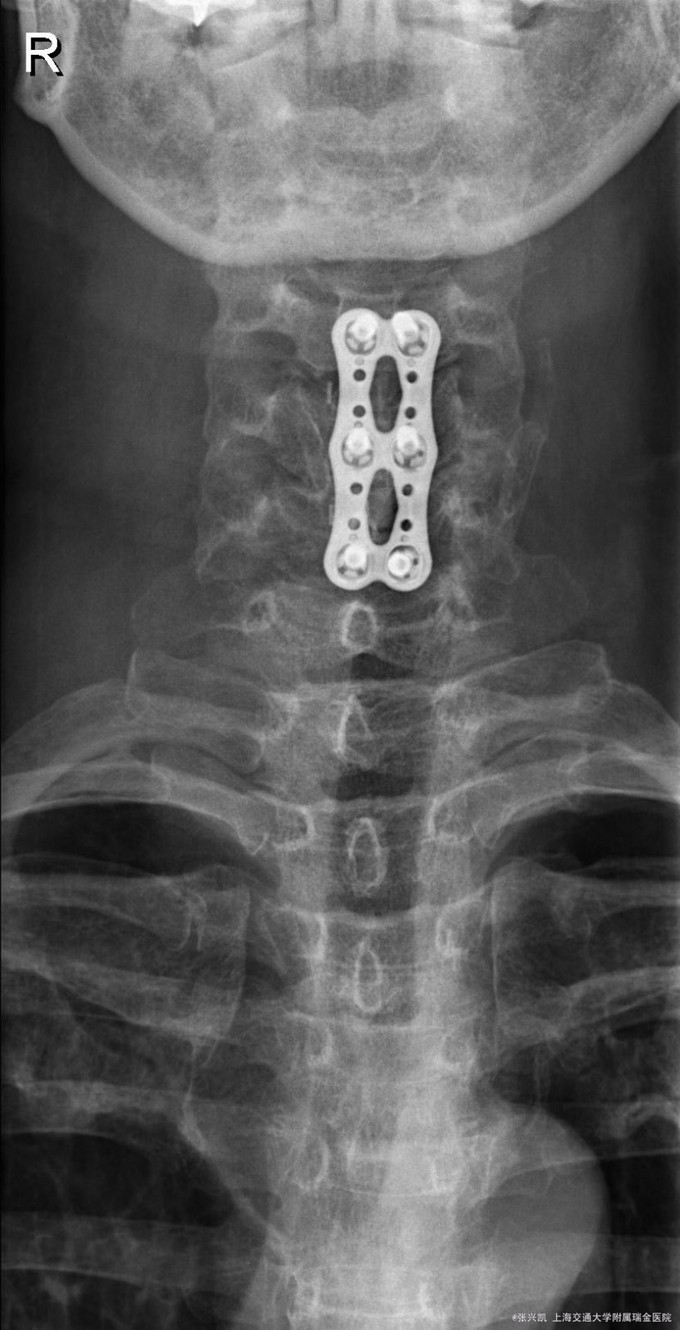

诊断:C4-5,C5-6椎间盘突出 治疗:颈椎前路减压融合内固定术

术后患者疼痛麻木感减轻,术后恢复良好。术后继续给予营养神经药物,促进神经恢复,减轻麻木感。